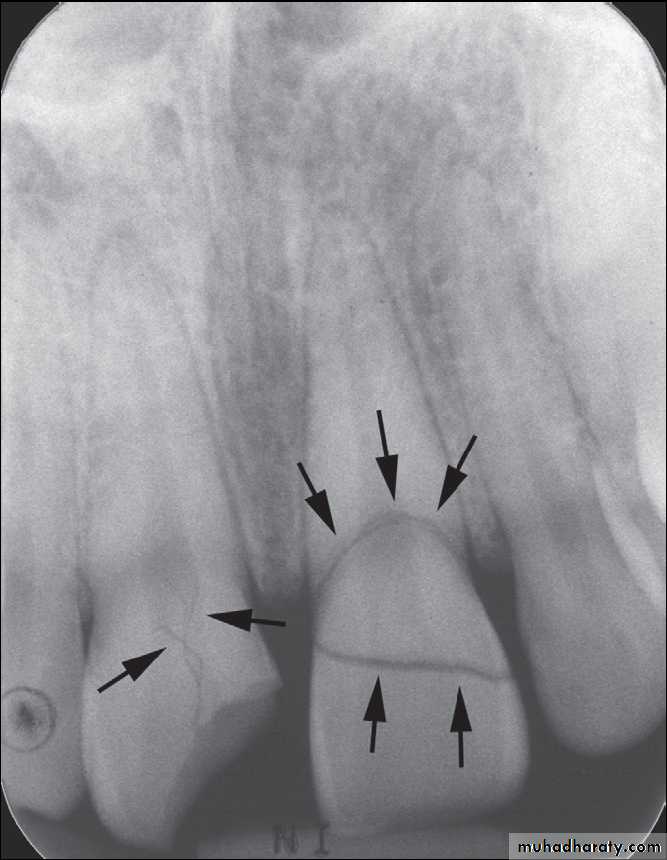

A nasal fracture, commonly referred to as a broken nose, is a fracture of one of the bones of the nose. Symptoms may include bleeding, swelling, bruising, and an inability to breathe through the nose. They may be complicated by other facial fractures or a septal hematoma.

Nasal bone fractures were classified into six types: Type I) Simple without displacement; Type II) Simple with displacement/without telescoping; IIA; Unilateral; IIAs) Unilateral with septal fracture; IIB) Bilateral; IIBs) Bilateral with septal fracture; Type III) Comminuted with telescoping or depression.